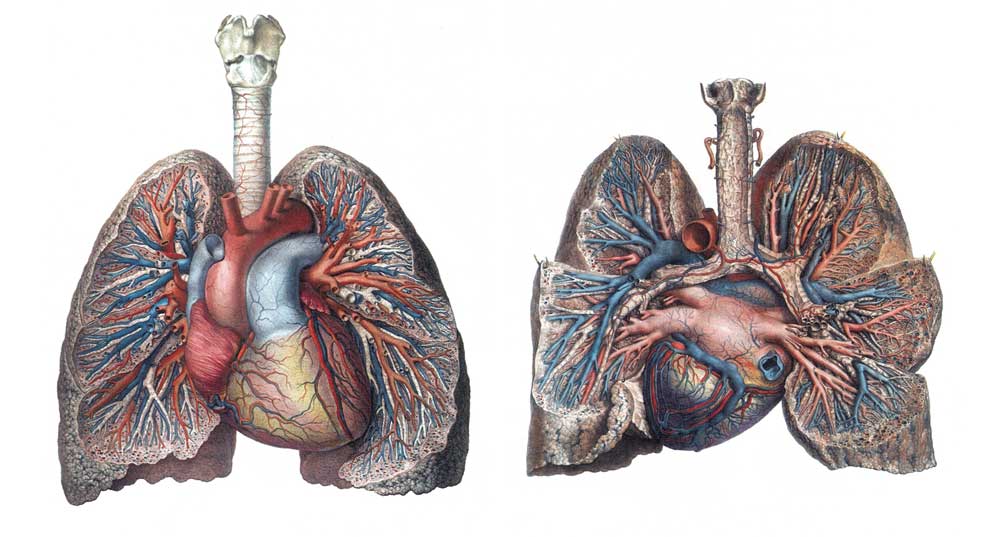

肺(p.66 肺)

肺は胸腔のおよそ80%を占め、心臓を入れる縦隔を間に左右に分かれる。肺は円錐を縦に半分に割ったような半円錐形をしていて、下面を肺底、頂点、にあたる上端を肺尖という。肺底は横隔膜に接し、肺尖は鎖骨の上方2~3cmにまで達する。円錐の断面にあたる内側面は心臓に接しているので少しくぼみ、その中央部に肺門がある。肺門からは気管支・肺動脈・肺静脈、そして気管支動静脈、リンパ管・神経なども出入りする。

肺葉(p.66 肺葉)

右肺の容積は約1,200mlで重さは約600gである。左肺は心臓がやや左側に片寄って存在するので少し小さく、その容積は約1,000mlで重さは約500gである。肺は深い切れ込み(裂)により肺葉に分かれる。右肺は上・中・下葉の3葉に、左肺は上葉と下棄の2葉に分かれる。肺の表面を詳細によく見ると直径1cmほどの多角形の小区画に分かれているのが見える。これを肺小葉という。肺小葉は小葉間結合組織により境されるが、成人の肺では呼吸によって吸い込まれた塵埃粒子の沈着により黒く見え、肺全体としては淡灰黒色を呈する。

胸膜(p.67 胸膜)

肺の表面は光沢のある薄い胸膜(臓側胸膜)でおおわれる。肺門では気管や肺動静脈を包んだあと、胸腔内面をおおっている胸膜(壁側胸膜)に移行する。肺門で折れ返った胸膜は、その間に胸膜腔という腔所をつくることになる。胸膜腔は少量の無色の漿液に満たされ、呼吸運動に伴う肺の自由な動きを可能にしている。胸膜腔の下端は下位肋骨内面では横隔膜との間に挟まれた狭い空間となり、胸膜洞と呼ばれる。胸膜炎では治癒したあとに胸膜の癒着が残り、肺の動きが制限される。胸膜腔は陰圧になっているが、肺や胸壁の損傷で胸膜腔に空気が入り大気圧と等しくなると、肺はその弾性のために小さく縮んでしまう。この状態を気胸という。